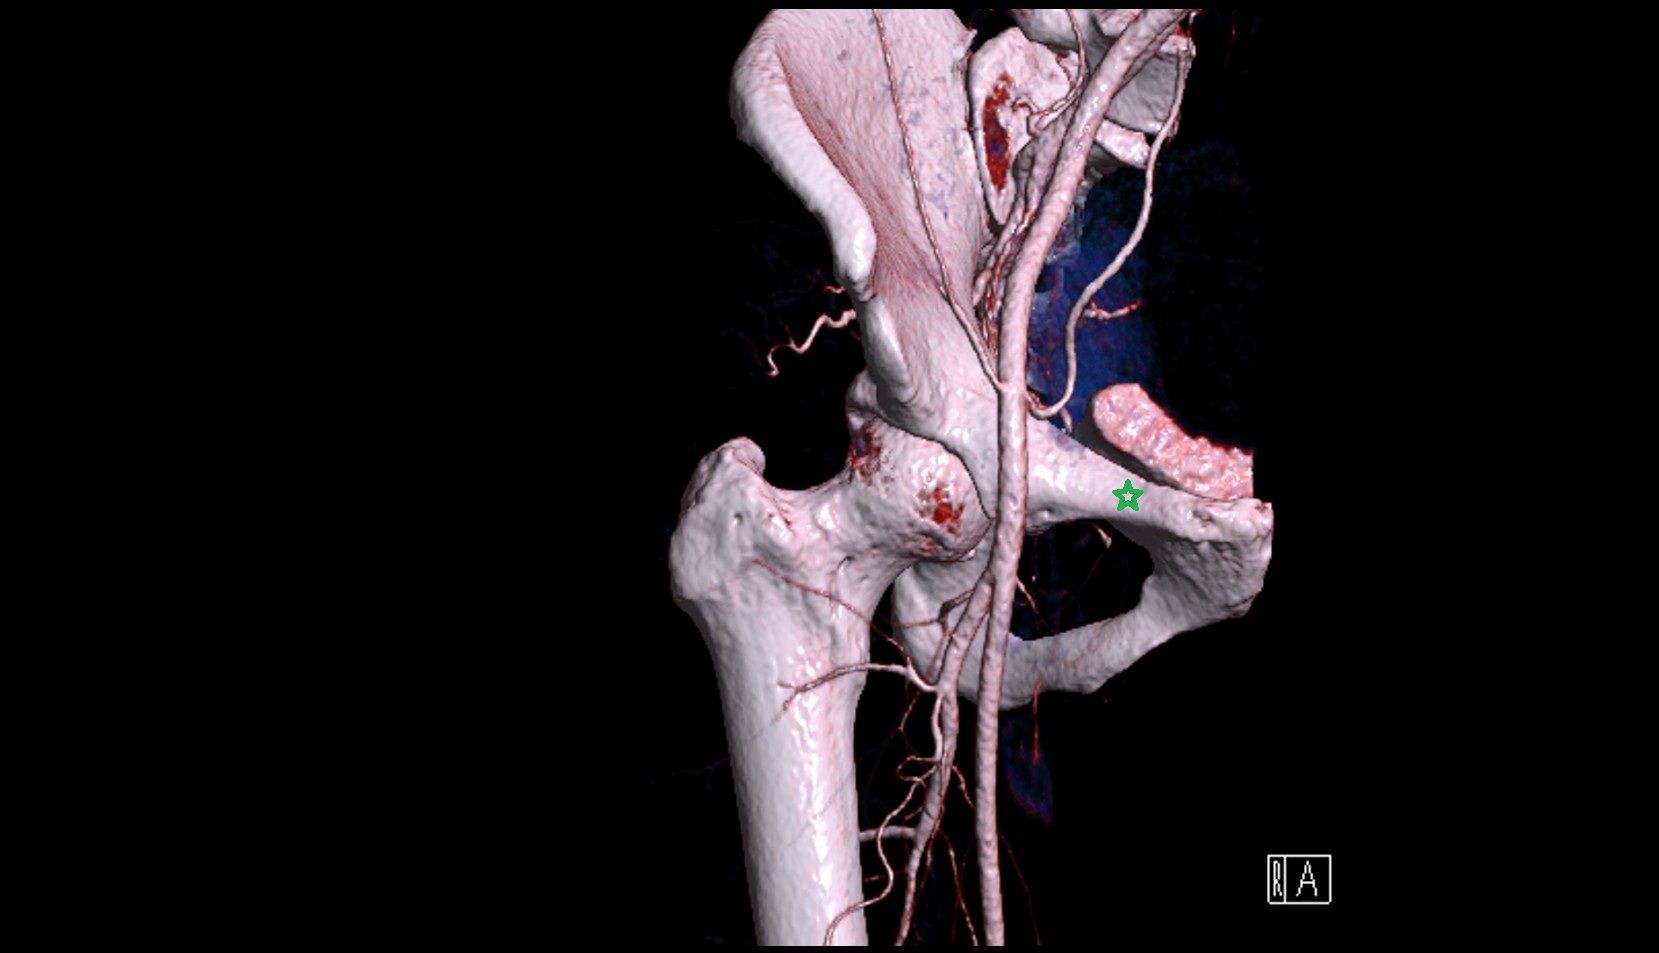

- Lateral circumflex femoral artery

- Deep femoral artery (profunda femoris)

- External iliac artery

- Femoral artery

- Internal iliac artery

- Medial circumflex femoral artery

- Obturator artery

- Superior gluteal artery